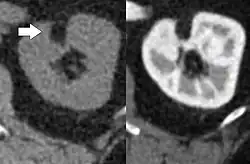

Angiomyolipoma in both kidneys (arrows) in computer tomography. The tumours are hypodense (dark) due to fat content. | |